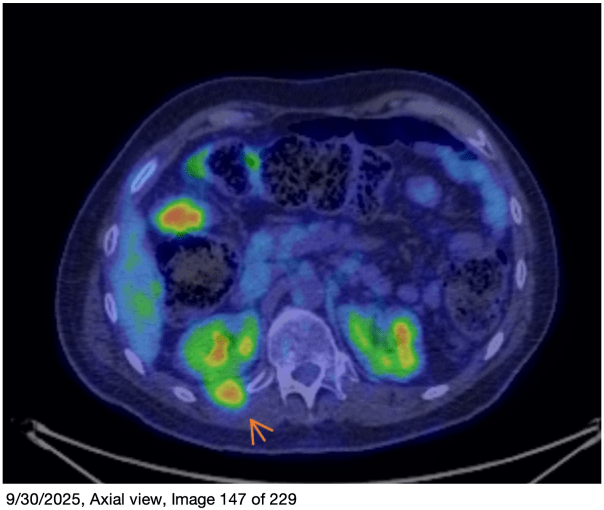

Until about a month ago, my pain was gradually increasing as my new tumors grew. Happily, my new treatment regimen is apparently working! For the last month or so, my pain level has been decreasing, allowing me to tune down my pain meds. Additionally, a PET scan just yesterday revealed that the new tumors, which weren’t responding to the old treatment regimen, are responding well to the new one.